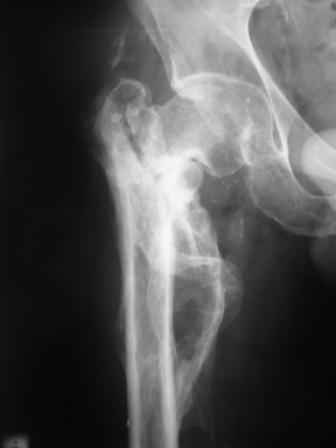

Уважаемый Глеб! Укорочение наверное побольше, да и наружно-ротационная установка скорее всего присутствует. Суставная щель прекрасная, головка живее всех живых. Ратую за подвертельную с латерализацией: исключает нарушение механической оси («исключает вальгус в коленe»), максимально удлиняет без натяжения m.iliacus. Для иллюстрации остеотомия-переделка (слава богу не автопеределка) у мужчины 65 лет.

PS. Извините за качество последнего снимка, рентгенограмма выполнена по м. жительства, там где был проведен синтез. Последний снимок выполнен через 2 мес. п\о, больной без разрешения начал наступать, слава богу все обошлось.